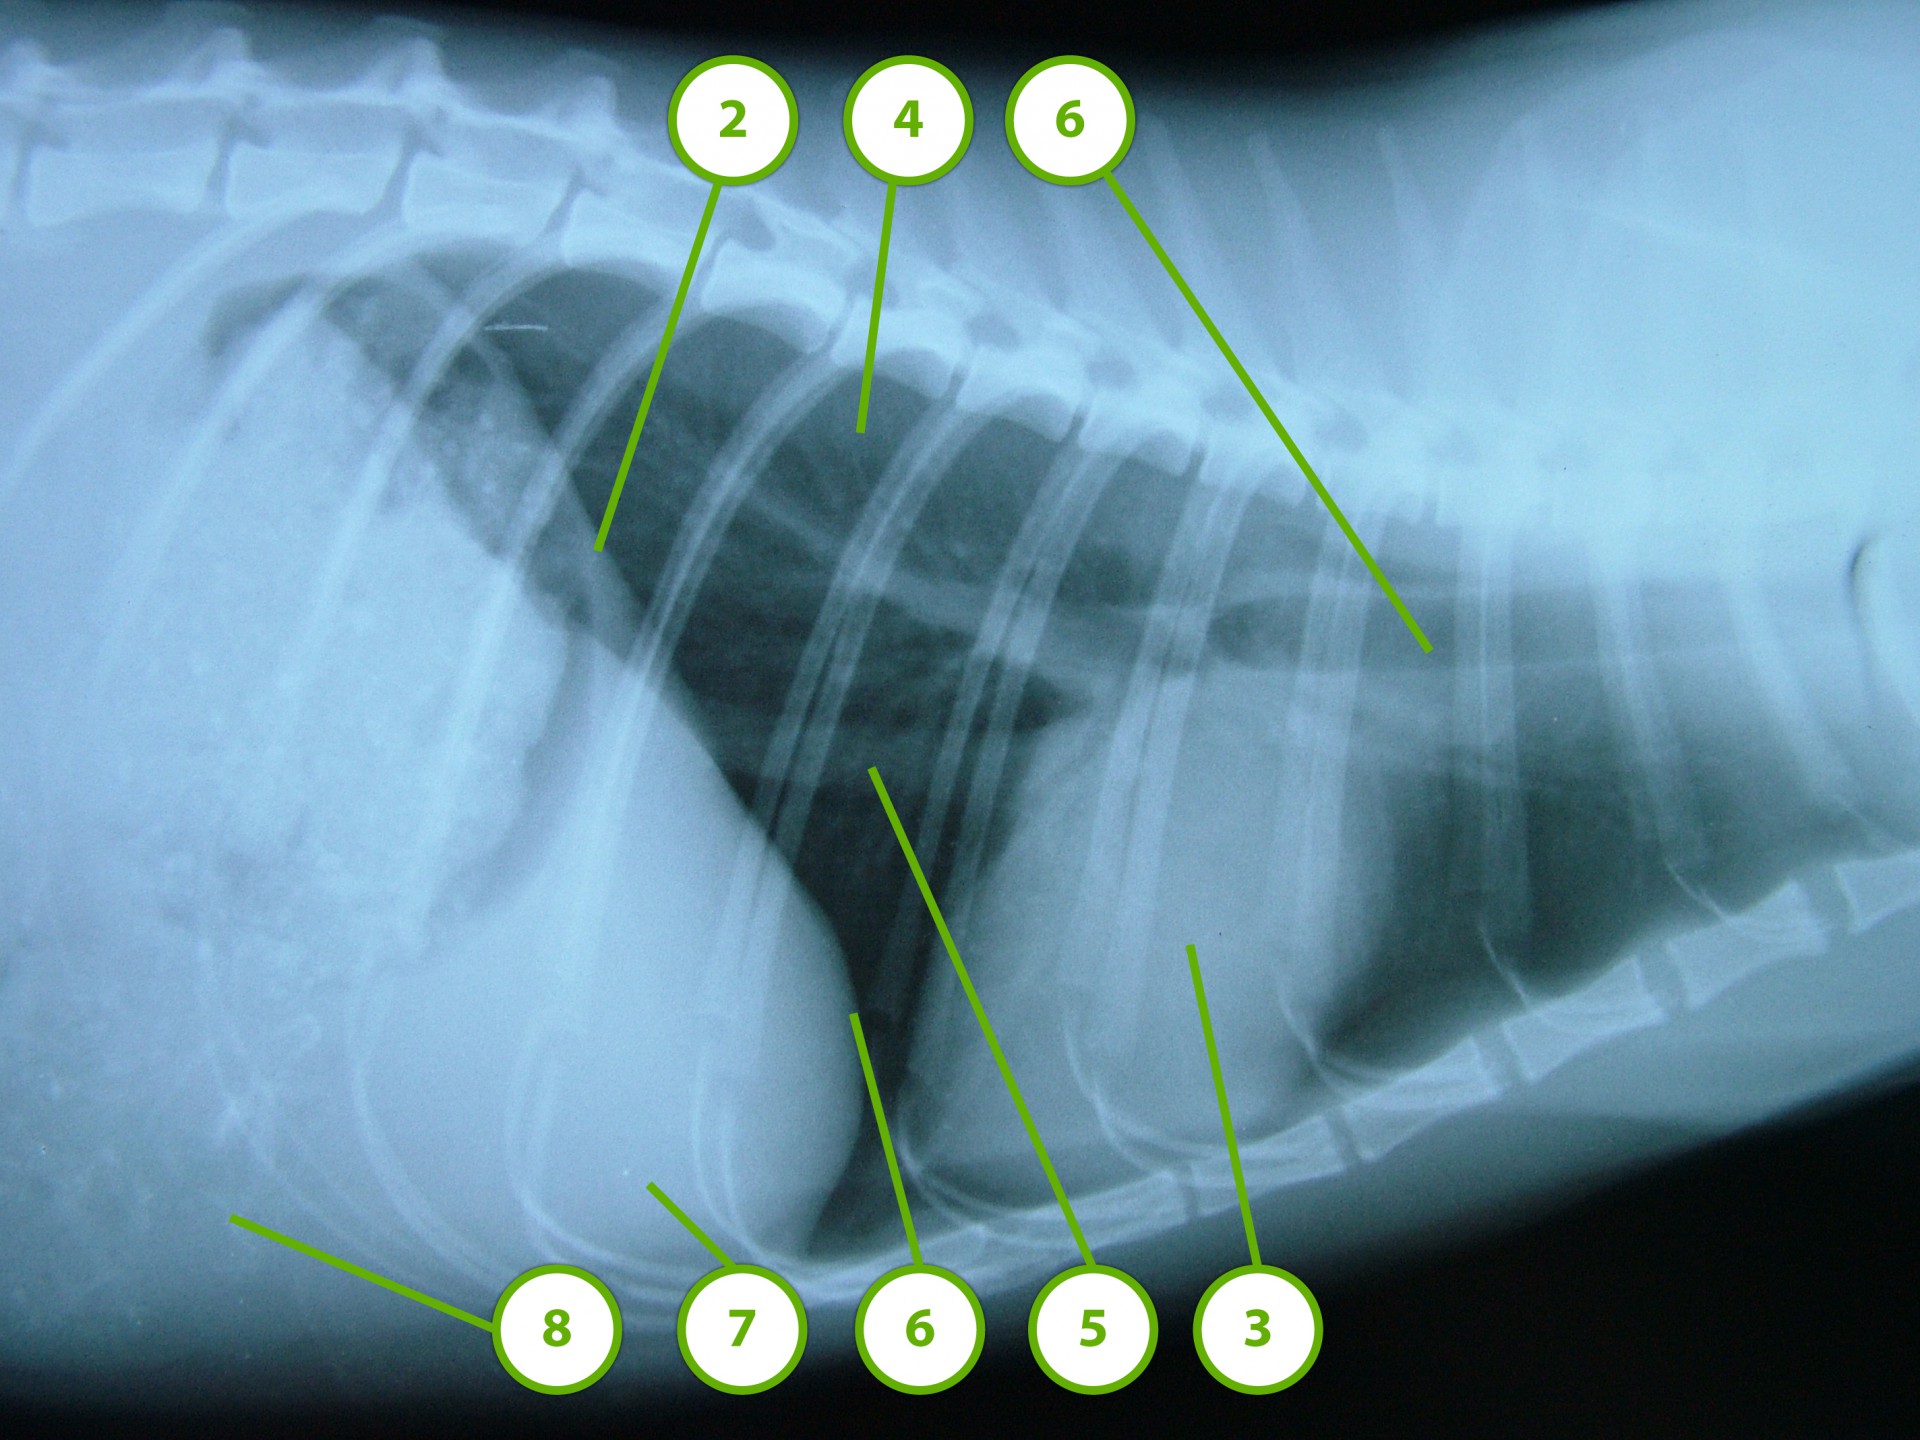

A rekeszizom veleszületett vagy szerzett sérülése, folytonosság hiánya következtében a hasüregi szervek a mellkasba nyomulnak, és összenyomják a tüdőt. Ennek következtében a tüdő nem képes a mellkas mozgását követni és elsősorban a belégzés folyamata korlátozottá válik.

• A fejlődési rendellenesség következtében kialakuló veleszületett rekeszsérv (hernia diaphragmatica congenitalis ) általában fiatal állatokban, alapvetően kétféle formában jelenik meg: az egyik formában a rekeszizom kisebb-nagyobb, a teljes vastagságára kiterjedő folytonossághiánya következtében a hasüregi szervek egy része a mellüregbe nyomul (valódi veleszületett rekeszsérv, hernia diaphragmatica congenitalis vara ).

• A másik esetben a nyelőcső rekeszen át történő haladása körül a rekesz rétegeiből csak a savóshártya kettőzet található meg, aminek a következtében ezen a területen a rekesz határoló funkciója gyengül, a hasüregi szervek(elsősorban a gyomor) a nyelőcső rekeszizomban található részén keresztül a mellüregbe türemkedik (hiatus hernia ).

Mindhárom rekeszsérv forma meglehetősen ritkán fordul elő. A diagnózis felállítása a kórelőzmény, a klinikai tünetek a mellkas röntgenvizsgálata, a hasüreg ultrahangos vizsgálata alapján lehetséges.A rekeszsérv műtéti ellátása során a legnagyobb kihívást az jelenti, hogy a hasüreg megnyitását követően a sérvkapun keresztül levegő kerül a mellüregbe, ezáltal az állat spontán légzése leáll, így a műtét teljes ideje alatt asszisztált lélegeztetésre van szüksége.A műtét során a mellkasba előesett szerveket reponáljuk, a rekesz folytonosság hiányát megszüntetjük és a mellkasban lévő szabad levegőt eltávolítjuk, ezzel biztosítva az állat spontán légzését. A műtétet követő napokban legfontosabb feladat a vérkeringés és a légzés folyamatos, kórházi körülmények közötti kontrolálása.Az idejében felismert és megfelelően ellátott veleszületett rekeszsérv jó eséllyel gyógyítható, a traumás eredetű sérv ellátásának eredményességét általában az egyéb szervek sérülése határozza meg.